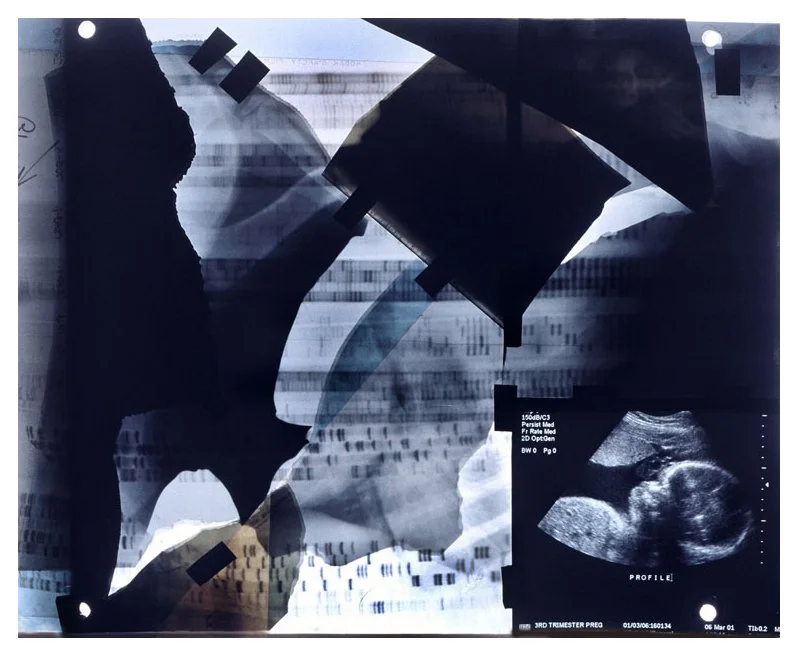

Insight is a series of collaged X-ray fragments, which were digitally composed into giclée prints. They speak not only of the body’s interior, but of the human experience it contains.

Drawn from DNA sequencing gels, mammograms, ultrasound scans, and cell cultures grown in Petri dishes, these compositions reframe diagnostic materials as metaphoric landscapes. What once served to identify illness becomes a language of line, texture, and light. They serve as a quiet meditation on fragility, resilience, and the unseen forces that shape us.

Each image in Insight is both an anatomical artifact and an artistic inquiry. Each one is part of my ongoing exploration of the relationship between Art, Science, and Medicine. Through digital layering and compositional play, I aim to dissolve the boundary between clinical detachment and emotional intimacy by inviting viewers to look inward and find meaning in the microscopic.